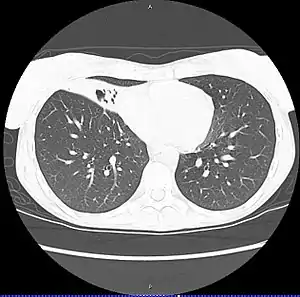

| CT scan of patient with right middle lobe aspiration and Mycobacterium avium infection consistent with Lady Windermere syndrome | |

MAC usually affects patients with abnormal lungs or bronchi. However, Jerome Reich and Richard Johnson describe a series of six patients with MAC infection of the right middle lobe or lingula who did not have any predisposing lung disorders.[18][19]

The right middle lobe and lingula of the lungs are served by bronchi that are oriented downward when a person is in the upright position. As a result, these areas of the lung may be more dependent upon vigorous voluntary expectoration (cough) for clearance of bacteria and secretions.

Since the six patients in their retrospective case series were older females, Reich and Johnson proposed that patients without a vigorous cough may develop right middle lobe or left lingular infection with MAC. They proposed this syndrome be named Lady Windermere syndrome, after the character Lady Windermere in Oscar Wilde's play Lady Windermere's Fan. However, little research has confirmed this speculative cause.[20]

- Chest X-ray or CT scan showing evidence of right middle lobe (or left lingular lobe) lung infection